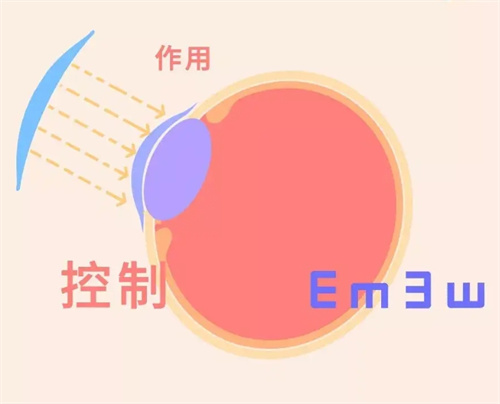

青少年近视防控门诊:150元/次(含全套基础检查)

争议项目:近视防控门诊的套餐定价(部分家长认为随访频次过高)